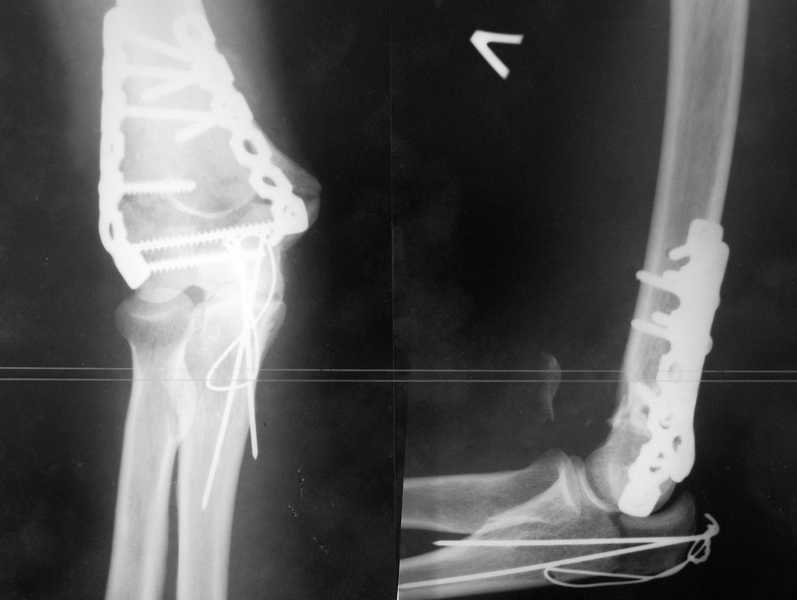

У пациентки 42 лет после операции остеосинтеза чрезмыщелкового перелома плеча, выполненной в нашей клинике 2 месяца назад, на контрольных R-граммах имеется гетеротопический оссификат по передней поверхности плеча. Оперирована по методике АО, после операции максимально рано начала заниматся ЛФК. В настоящее время основная жалоба пациентки на ограничение сгибания в локтевом суставе. Клинически объем движений: сгибание 90 градусов, разгибание 170 градусов, ротационные движения в полном объеме. Привожу снимки сразу после операции и через 2 месяца. (На рентгенограммах после операции в мягких тканях по передней поверхности плеча имеется небольшой костный фрагмент, но его ширина во фронтальной плоскости не более 1 мм., обнаружен был по снимкам после операции. Интраоперационно основные крупные фрагменты отрепонировались хорошо, объем движений был сгибание до 75 градусов, разгибание 175 град.) Пациентка неудовлетворена объемом сгибания, хотя была предупреждена о высокой вероятности ограничения движений. Профилактика гетеротопической оссификации (прием индометацина) не проводилась, т.к. имелась язвенная болезнь, да и эффект от его приема считаю сомнительным. Вопросы: 1.Стоит ли вмешиваться и пытаться удалить экзостоз? Если да,то в какие сроки и каким доступом лучше идти? 2. Оставить все как есть? 3. Не поможет ли ударно-волновая терапия либо какая-то другая методика? Буду благодарен за все ответы и оценки своей работы. С таким осложнением столкнулся впервые.

Снимки сделаны по правилам укладки, но объем сгибания сейчас 90 градусов. Пациентка хочет большего объема сгибания.

В данном случае лучше ни чего не трогать до года, произойдет консолидация, затем при удалении металла можно будет сделать артропластику с удаление оссификата и освободить передний отдел, а возможно к тому времени и задний. Пациентка должна поддерживать имеющийся объем движений.

Доступ обычно наружно-боковой без опаски, если не удается все достать, то внутренний боковой с выделением локтевого нерва(безопасней и спокойней). ФЗТ на локтевом суставе обычно без эффекта.